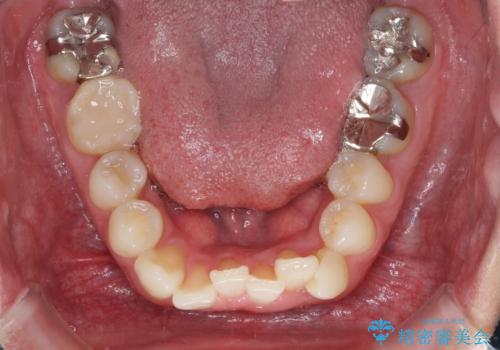

- 右下奥歯の虫歯がしみて痛いとのことで来院された患者様です。

神経近くにまで及ぶ大きな虫歯でしたが、速やかに処置を行い、痛みは即日解消されました。

虫歯が大きかったため、クラウンによる補綴治療が必要になる旨をお伝えしたところ、矯正治療にも興味があるとのことでした。

短期間で手間のかからない方法がご希望でしたので、ワイヤー装置による矯正治療を行うこととし、矯正治療後に右奥2歯をセラミッククラウンにて補綴することとしました。